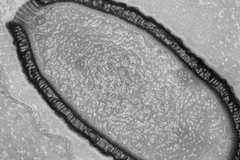

Việc hồi sinh một loại virus từng tồn tại cách đây 30.000 năm là lời cảnh báo rằng những nguồn bệnh chưa được biết tới, có thể sẽ ''thức tỉnh'' bởi quá trình nóng lên toàn cầu.